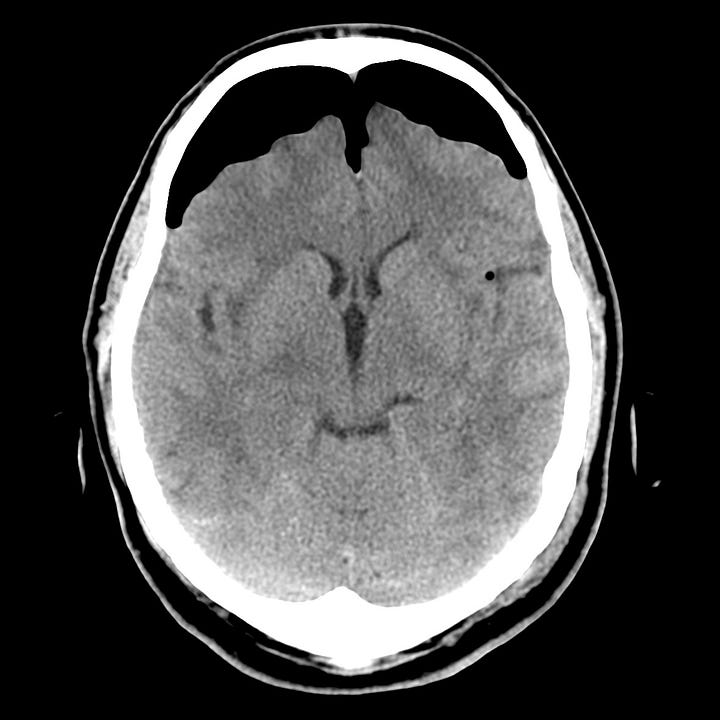

Pneumocephalus following facial trauma with orbital roof and ethmoid fractures. Small amount of air anterior to the right frontal lobe, between the ethmoid bone and the olfactory cortex, and within the right superior orbit. This air is not under tension, but it indicates that the skull base periosteum has been breached and that the subdural space communicates with one of the facial sinuses (in this case the ethmoid air cells). The patient is therefore at increased risk of CSF leak or meningitis.

Rarely, a dural laceration can act like a one-way check valve, permitting inflow of air, but preventing its egress. By this mechanism, intracranial air pressure can exceed tissue pressure and compress the brain. In the supine patient, this is most evident in the anterior cranial fossa and results in a peaked appearance of the frontal lobes (Mount Fuji sign).

Tension pneumocephalus due to temporal bone fracture. Bifrontal subdural air collections with mild compression of the frontal parenchyma. Opacified left mastoid air cells are consistent with an acute tem- poral bone fracture. Air in the cisterns and left sylvian fissure indicate arachnoid injury.